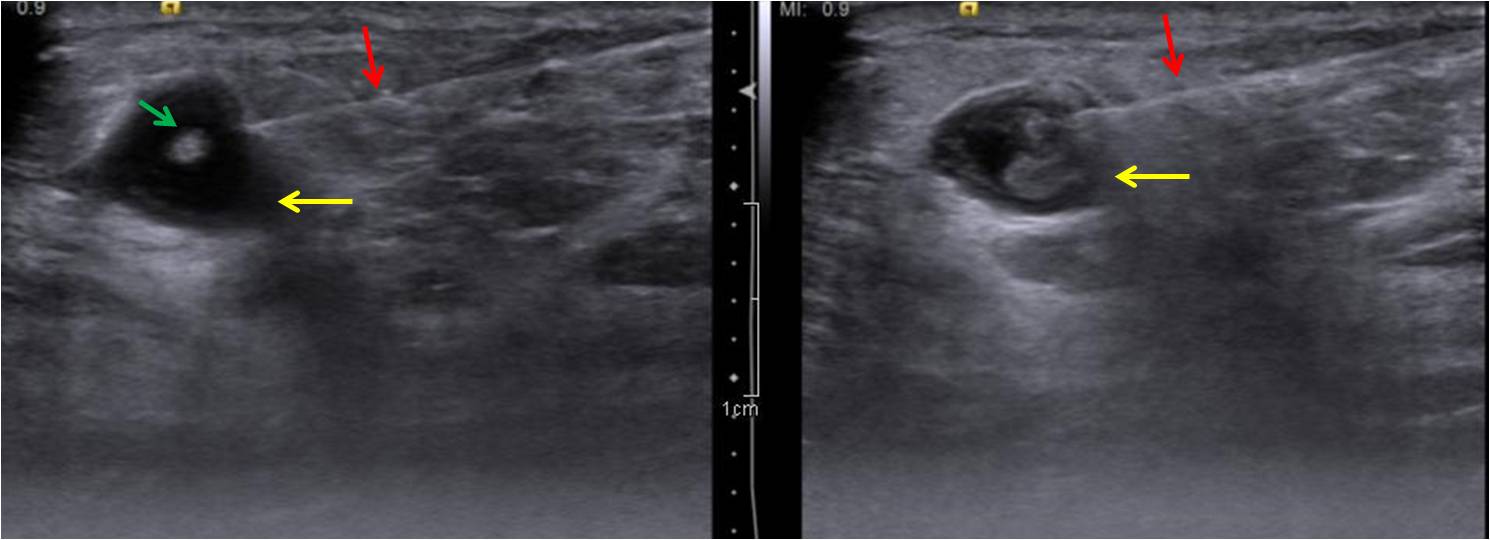

An asymptomatic 49-year old lady underwent a screening mammogram [Figure 1.]. In a background of heterogeneously dense breast parenchyma there was a 10mm round mass in the upper-outer quadrant of the left breast (anterior-third) with obscured posterior margins. No calcifications, spiculated mass or significant axillary lymph nodes were noted. She was recalled for further clinical assessment which revealed a palpable lump and an ultrasound (US) was advised. Sonomammogram [Figure 2.], in the area of mammographic abnormality, revealed a 12 x 10mm thick walled cyst with a 2mm polypoidal echogenic mural nodule arising from it’s non dependant wall. No other focal abnormality was seen in the rest of the left breast. Mildly enlarged nodes with slightly thickened cortex were noted in the left axilla. Ultrasound-guided biopsy of the complex cyst was performed [Figure 3.] with no complications. Histopathology [Figure 4] revealed larva of the cysticercal parasite (racemose cyst wall) with a surrounding giant cell reaction. Clinical follow-up after a two-month course of albendazole showed no palpable abnormality and USG [Figure 5.] in the region of abnormality showed resolution of the cyst.